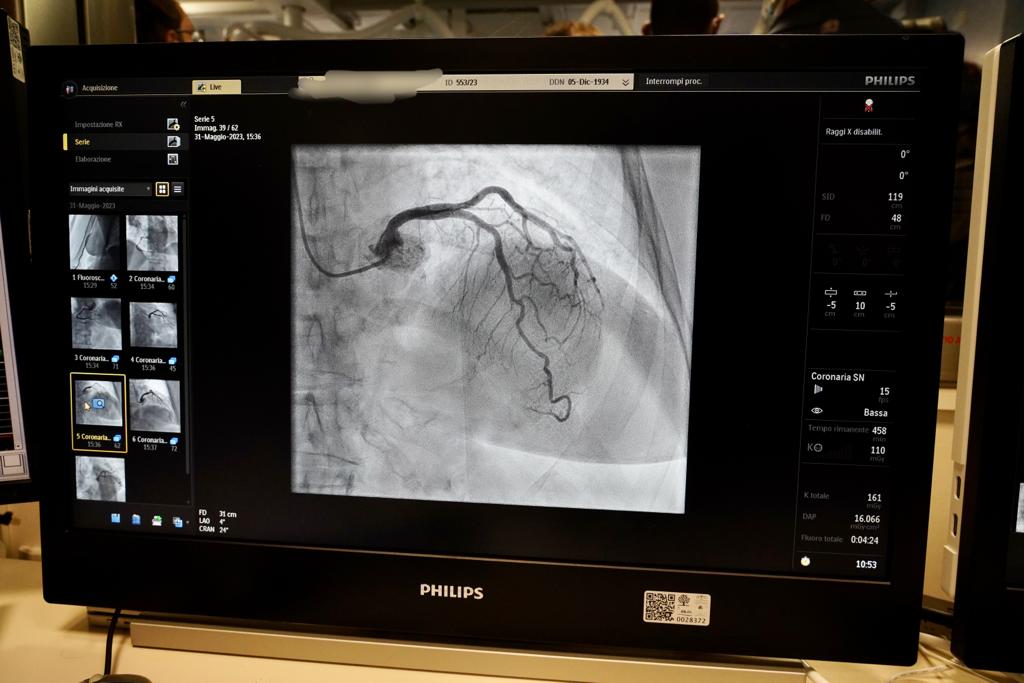

La Cardiologia e i servizi di Emodinamica e di Elettrofisiologia dell’Ospedale Di Venere possono contare su due nuovi angiografi con tecnologia digitale che hanno rivoluzionato tempi e qualità delle procedure diagnostiche ed interventistiche cardiache. Si tratta di attrezzature moderne e performanti che, da un lato, assicurano meno radiazioni a protezione di pazienti e operatori sanitari, e, dall’altro, offrono una elevata risoluzione delle immagini che consente, quindi, di ridurre i tempi di esecuzione degli esami o degli interventi, con una precisione estrema delle prestazioni.

Una delle due apparecchiature - la più recente - è stata acquisita con fondi PNRR, nell’ambito della Missione 6 Salute (Ammodernamento del parco tecnologico e digitale ospedaliero - Grandi Apparecchiature) ed è stata installata nella sala di Emodinamica dedicata alla esecuzione di coronarografie e procedure di angioplastica. La seconda apparecchiatura viene, invece, impiegata per impianti di: pacemaker, defibrillatori, defibrillatori biventricolari e loop recorder. L’investimento complessivo è stato di 960mila euro.

A contraddistinguere le macchine sono gli algoritmi di elaborazione e ottimizzazione dell’immagine che offrono la miglior qualità degli elementi visualizzati, ad una frazione della dose radiante.

L’angiografo per le procedure coronariche è installato a soffitto che consente un posizionamento flessibile e liberamente girevole dei monitor per un eccellente angolo di visione. Il piano su cui viene posizionato il paziente è completamente radiotrasparente, con elevata capacità di carico e con ampia gamma di movimenti. Il posizionamento del paziente si esegue senza sforzo in maniera estremamente agevole rendendo più facile lo spostamento dei pazienti con maggior peso. Un meccanismo sicuro blocca il piano del tavolo in posizione per impedirne il movimento.

Elemento fondamentale della catena di immagine è il detettore studiato appositamente per applicazioni cardiologiche.